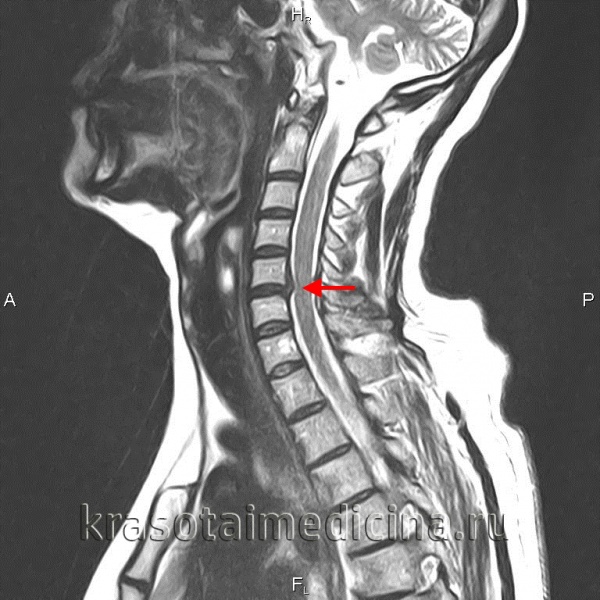

МРТ шейного отдела позвоночника. Межпозвонковая грыжа в сегменте С5-С6, отслаивающая заднюю продольную связку